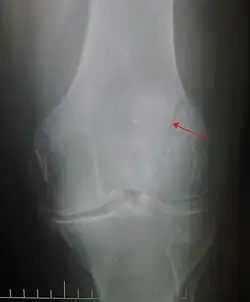

The patella can break in various ways depending on the way it is injured, and into two or more pieces.[1] Types include transverse, the most common, with one fracture line;[5] marginal; osteochondral; and the rare vertical type, or stellate, where a direct compression force gives rise to a comminuted pattern.[5][7] Patella fractures can be further classified as displaced, where the broken ends of bone do not line up correctly and separate by more than 2mm, or undisplaced and stable where pieces of bone remain in contact with each other.[1][7] If fragments of patella bone stick out from the skin it is known as an open patella fracture, and closed if the overlying skin is intact.[1]

Vertical patella fracture